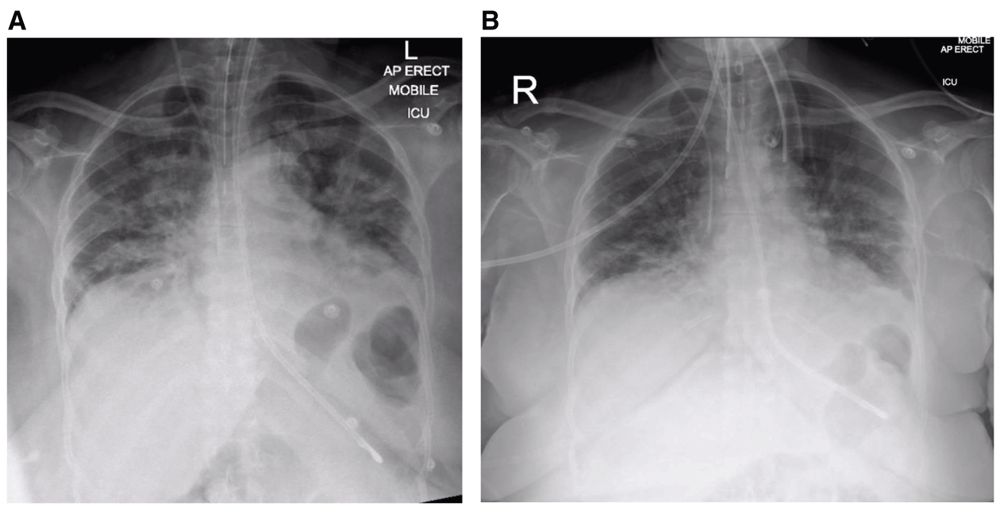

Rapidly Progressive Ards Secondary To Covid 19 Infection Eurorad